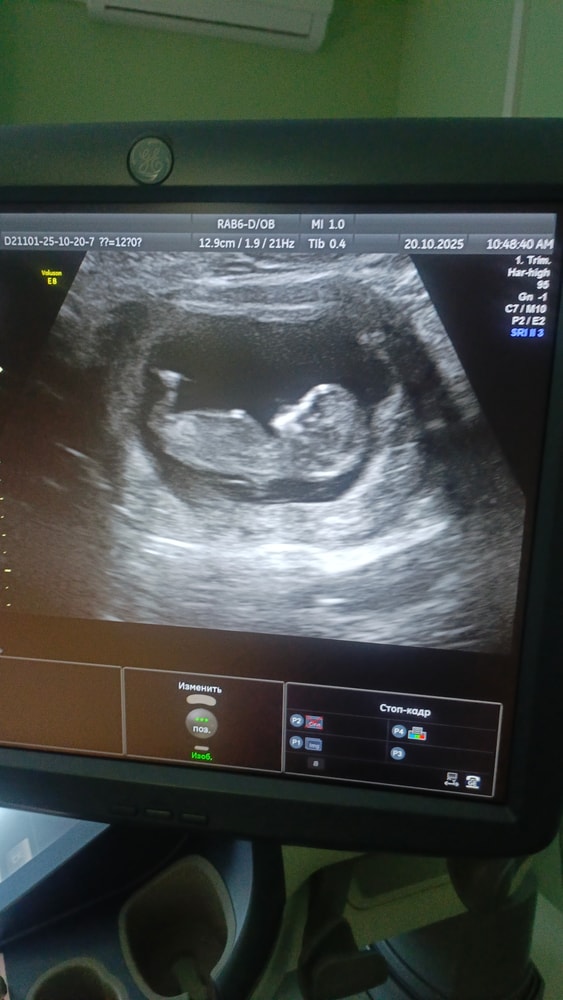

Мария Кокорина в Благополучная беременность 2 месяца На кого похож? Затрудняюсь с категорией Мальчик или девочка? Или так не понятно? 🤷 Посмотрите еще 20 записей на эту тему Лучший ответ Екатерина Так нет на фото полового бугорка 21.10.2025 Ответить Отменить Ответить Лера Сдайте кровь на определение пола, точность 99%) 21.10.2025 Ответить Светлана Бугорка не видно 21.10.2025 Ответить Таня Кровь на определение Пола , рекомендую ) 21.10.2025 Ответить Даша На таком сроке рано говорить на кого похож. 21.10.2025 Ответить Что думаете? Какие прививки обязательные для детей? Чаты Беременных Выберите чат: Январята-2026 Февралята-2026 Мартята-2026 Апрелята-2026 Майчата-2026 Июнята-2026 Июлята-2026 Августята-2026